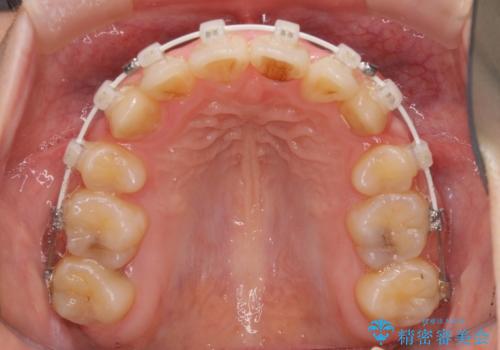

- 審美装置

結婚式の予定があったため、まずは前歯をきれいに整えるようにしました。

結婚式の時には一時的に前歯の装置を外し、口元を気にせず笑える結婚式を迎えることができました。